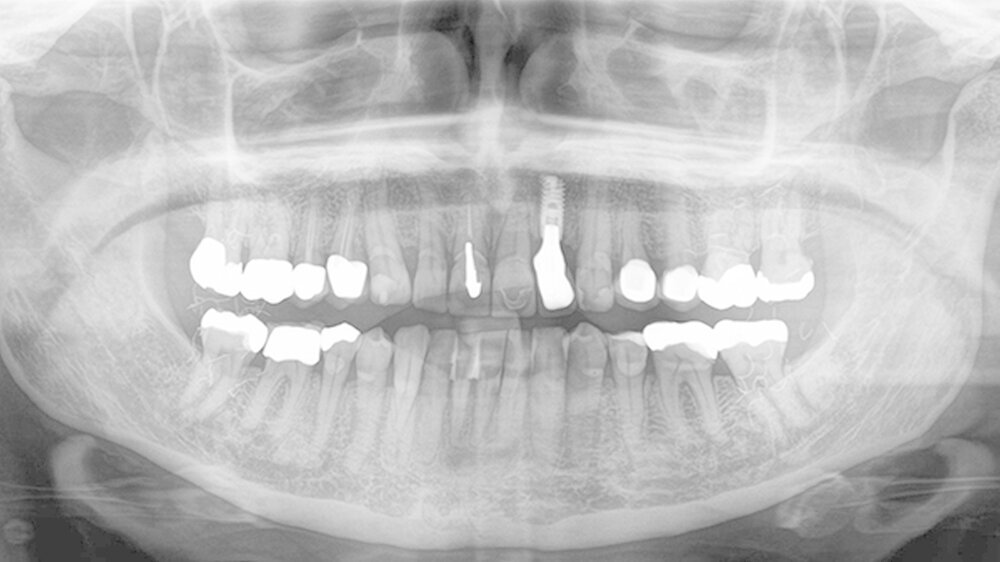

Im September 2016 stellte sich die Patientin erneut zu einer Kontrolluntersuchung in unserer Praxis vor. Es wurde ein neues OPG zur Beurteilung der Implantatversorgung an Regio 22 aufgenommen (Abbildung 2). Wieder traten hierbei diese zerstreuten, kleinfädigen Verschattungen im Seitenzahnbereich auf.

Ein Vergleich der beiden Röntgenaufnahmen zeigte identische Strukturen an gleicher Position. Der Behandler wunderte sich über diese in über 35 Jahren Berufserfahrung noch nie - und jetzt zum wiederholten Mal - gesehene Röntgenverschattung. Auf die Frage, ob sie wüsste, woher diese Fusseln stammen könnten, antwortete die Patientin, sie habe vor vielen Jahren ein Goldfadenlifting erhalten, das die Verschattungen möglicherweise verursacht haben könnte.